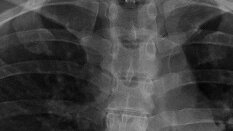

Что из себя представляет рентген грудного отдела позвоночника? Это стандартное 2-х мерное рентген-исследование, проводимое как правило в двух проекциях(прямой и боковой). Рентген грудного отдела позвоночника(ГОП), не подразумевает никакой предварительной подготовки, исследование проводиться лёжа, на спине и на боку, предварительно снимаются все металлические украшения...